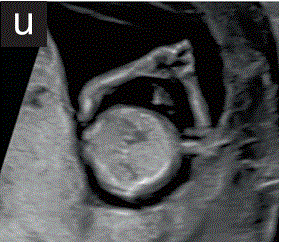

9 四肢

9.1 在11+0~14+0周超声检查中,应注意上肢和下肢三段的存在和双脚的存在和正常方向(图2t和2u)。

胎儿mt是什么检查什么疼吗【文献学习/规范指南】ISUOG实践指南(2023更新): 11-14周胎儿超声检查(全文)_https://www.jmylbn.com_新闻资讯_第28张

图2 11+0至14+0周时,可作为详细胎儿超声检查的一部分获得的解剖图。

(t)双下肢冠状面图,上肢、小腿、足三节段清晰可见。

(u)双侧上肢切面,上臂、下臂、手三节段清晰可见。妊娠早期的胎儿通常表现为张开的手,这可能有助于评估胎儿的手和手指。